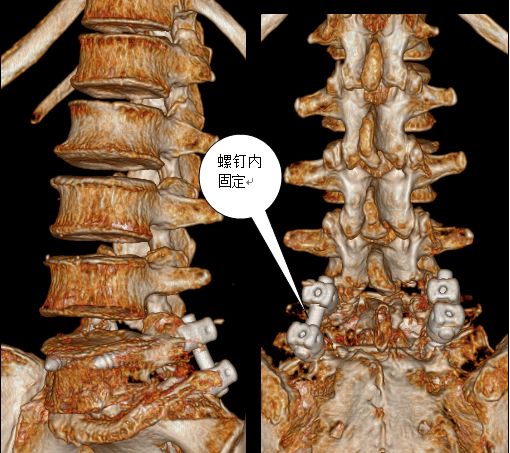

在完善了相关检查后刘阿姨被确诊为腰椎滑脱症—腰5椎体II度向前滑脱。

腰5椎体2度

向前滑脱

脊髓受压变形

术后腰5椎体

完全复位

脊髓压迫

完全解除

腰椎内

固定术后

螺钉内固定